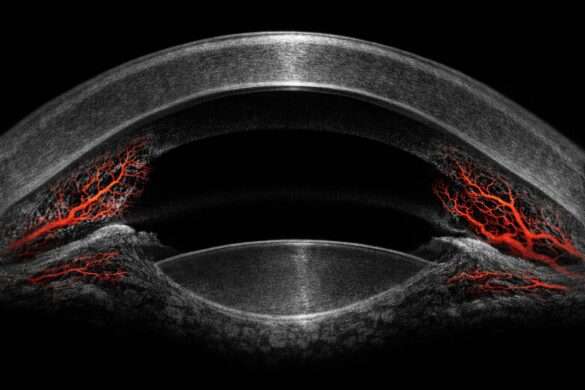

水平断層像(2D画像)

前眼部OCTを代表するような造影画像で、CASIA2では各種OCTの前眼部オプションとは異なり隅角全体を描写することができます。

前眼部の全体画像

CASIA2Advanceから大きく変わった機能の一つで、眼全体の画像をカラー表示することができます。

これにより血管の描写や角膜の混濁が見やすくなりました。